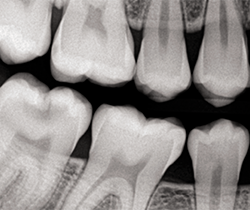

A 14-year-old patient presented to our office for a new patient examination. He had just completed orthodontic treatment and he had several large posterior caries and areas of defective enamel on his anterior and posterior teeth (Figs. 1-5). After a thorough examination and consultation with the patient and father, it was determined that the large caries on teeth #14DO, 18OB and 31OB should be sealed with large fillings, the defective enamel be treated with CTx4 toothpaste and CTx3 oral rinse (CariFree), and monitored as he gets older. The patient was appointed for caries removal and direct restorations to be placed at his next visit.

Fig. 1 Fig. 2